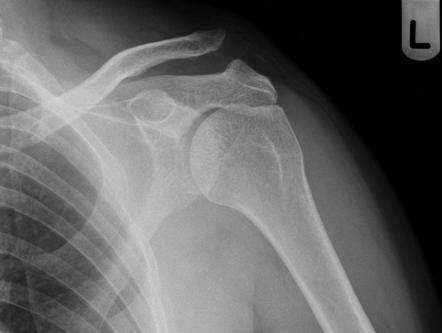

Hình ảnh trật khớp cùng đòn chụp x quang ở tư thế trước và sau

3. Hình ảnh trật khớp cùng đòn trên x quang ở tư thế trước và sau

- Chụp vai với các tư thế trước-sau, bên theo tiêu chuẩn, tuy nhiên chụp với tư thế Zanka cho cái nhìn rõ ràng nhất về khớp cùng đòn. Các tia X sẽ chiếu nghiêng khoảng 10-15 độ hướng lên đầu, để quan sát rõ nhất người bệnh nên xách mỗi bên khoảng 5kg và so sánh giữa 2 bên trên phim XQ.

Chụp với tia cường độ cao có thể cho phép phân biệt các dạng tổn thương giữa type I và II, đặc biệt quan trọng hơn trong phân biệt giữa type II và type III.